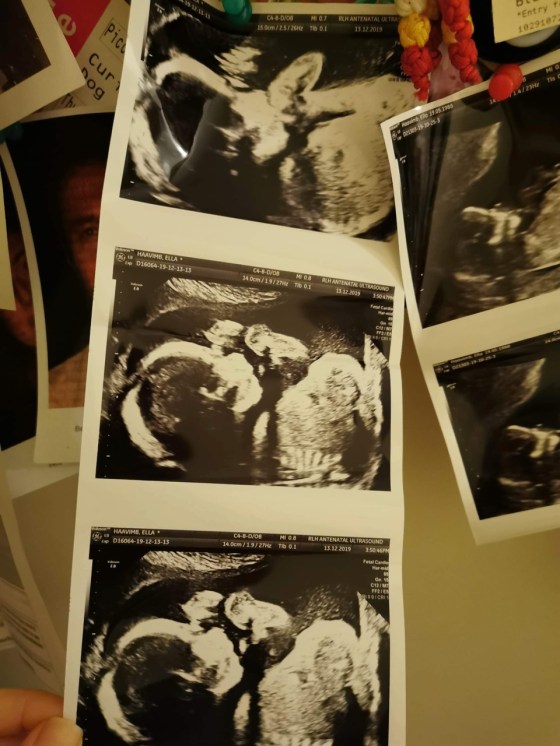

En liten baby finns i Ellas mage och det gör oss alla lite upprymda. vi är liksom i Dröm-mood allihopa! Ella och Ekin bor ju i London så vi har ju inte fått klappa babymagen på hela tiden!

Babyn ligger där inne och suger på tårna och har det bra. Ella mår också bra. Det gläder mig, Ganga, eftersom jag själv var extremt illamående och kräktes hela graviditeterna.